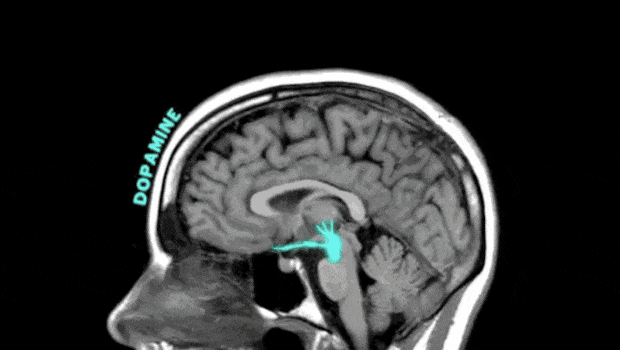

靠奶茶、蛋糕等来缓解情绪,其实是借助血糖快速上升,刺激多巴胺短暂释放,从而获取即时快感。所以情绪管理能力较差的人,会简单粗暴地通过食物来抑制或缓解负面情绪。